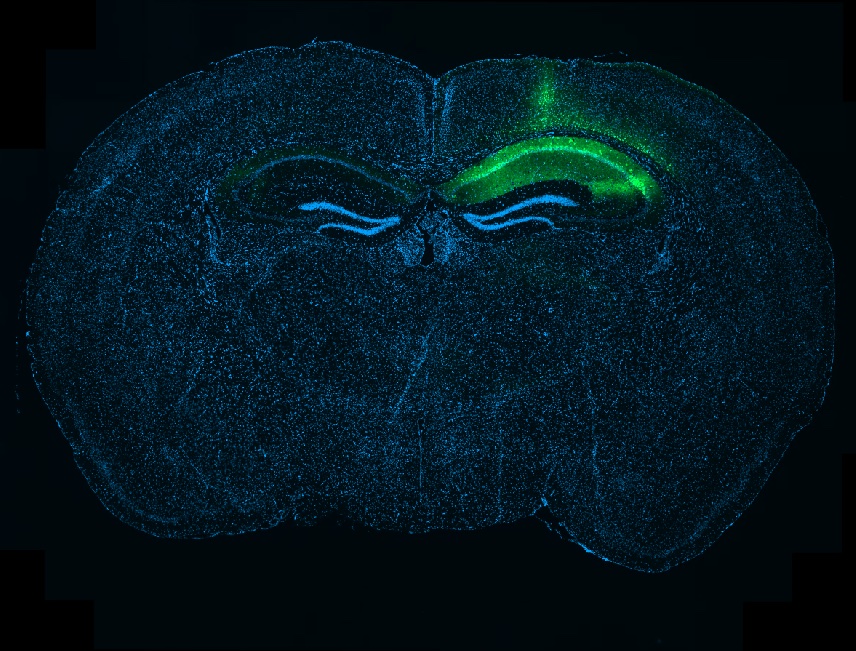

Whole-brain section showing local tau expression in the hippocampus

Banner image: Whole-brain section showing local tau expression in the hippocampus after a targeted injection, visible here as the green signal on one side of the brain. Credit: Robert Ellingford